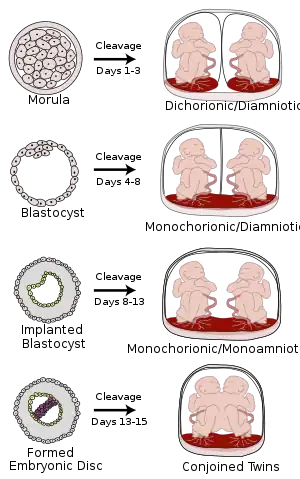

Monoamniotic twins are identical or semi-identical twins that share the same amniotic sac within their mother's uterus.[1] Monoamniotic twins are always monochorionic and are usually termed Monoamniotic-Monochorionic ("MoMo" or "Mono Mono") twins.[1][2] They share the placenta, but have two separate umbilical cords. Monoamniotic twins develop when an embryo does not split until after formation of the amniotic sac,[1] at about 9–13 days after fertilization.[3] Monoamniotic triplets or other monoamniotic multiples[4] are possible, but extremely rare.[1] Other obscure possibilities include multiples sets where monoamniotic twins are part of a larger gestation such as triplets, quadruplets, or more.

Ultrasound is the only way to detect monoamniotic-monochorionic twins before birth.[4] It can show the lack of a membrane between the twins after a couple of weeks' gestation, when the membrane would be visible if present.[4]